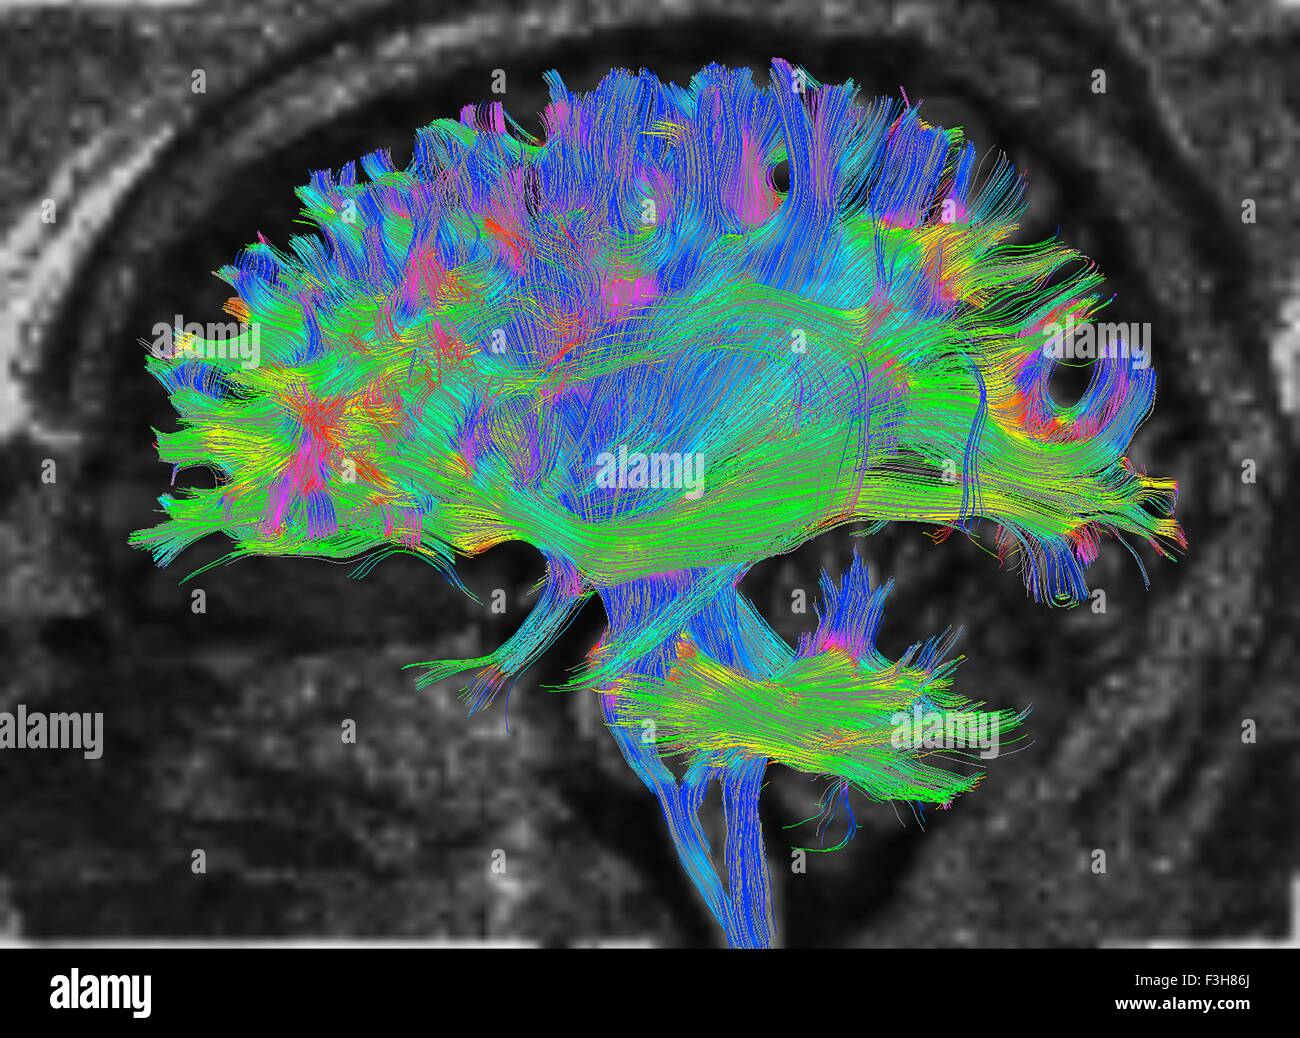

Diffusion tensor imaging (DTI) tractograpy. The color-coding of

Using Diffusion Tensor Imaging (DTI), axonal fiber tractography

A) Diffusion tensor imaging (DTI)-based whole-brain tractogram in